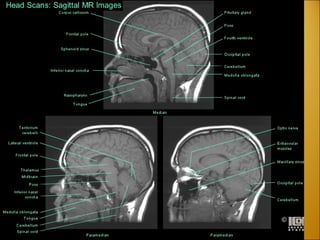

Dura mater (reflections) Crista galli  Falx cerebri  Sinus sagittalis inferior  Incisura tentorii - Tentorial incisure  Sinus rectus  Confluens sinuum  Tentorium cerebelli  Sinus petrosus superior  Sinus sphenoparietalis  Diaphragma sellae  Arteria carotis interna  Nervus opticus  Foramen magnum

Dura mater (reflections)Crista galli Falx cerebri Sinus sagittalis inferior Incisura tentorii - Tentorial incisure Sinus rectus Confluens sinuum Tentorium cerebelli Sinus petrosus superior Sinus sphenoparietalis Diaphragma sellae Arteria carotis interna Nervus opticus Foramen magnum